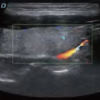

DW-L50 Exp

DW-L50 Exp

Aparato de Diagnóstico Ultrasónico Digital a Color Completo de Tipo Laptop

El DW-L50 Exp, impulsado por la avanzada plataforma de ultrasonido ST-U, ofrece imágenes ultra claras en todo momento. Con una movilidad y adaptabilidad sobresalientes, funciona de manera fiable en diversos entornos clínicos complejos. Su introducción permite que más instituciones médicas accedan a tecnología de ultrasonido rentable y de alto rendimiento.